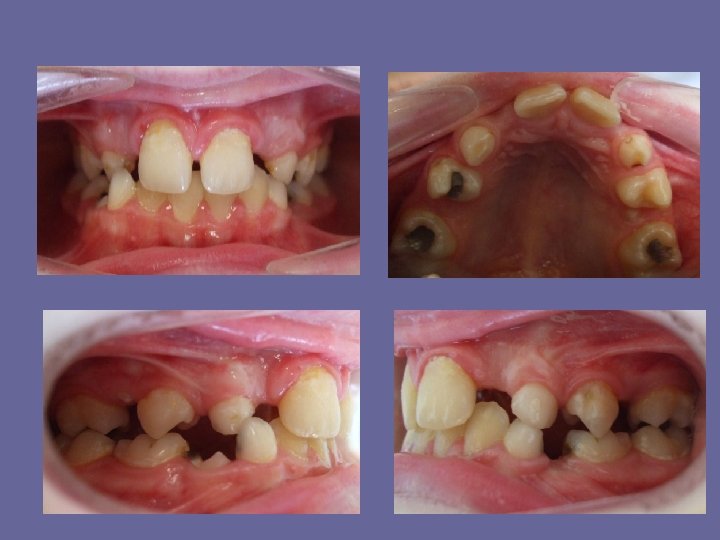

THE DECIDUOUS DENTITION The stage of deciduous teeth represents an important part of ontogenetic development when usually an exact diagnosis can be established as well as a further prognosis can be assessed. Existence of the deciduous dentition can be divided into three stages: 1. the eruptive stage 2. the functional stage 3. the stage of make-ready for eruption of permanent teeth

THE DECIDUOUS DENTITION The regular deciduous dentition has these characteristic features: • both arches have semicircular shape • the long axises of the teeth are parallel and curve of Spee is missing

THE DECIDUOUS DENTITION • every tooth ocludes with two antagonists except lower central incisors and upper second molars • upper arch overlaps the lower arch, there is small frontal and lateral overjet

THE DECIDUOUS DENTITION • the second deciduous molars are flush distally. It occurs in 70 -80% cases. However, the negative step may be also present if the upper second deciduous molar is as wide as lower or the positive step if the lower second molar is too wide in relation to upper or if there is class II relationship of the dental arches.

THE DECIDUOUS DENTITION • there may be spacings distal to the lower canines and mesial to the upper canines called primate spacings • incisors may be spaced The second phase is biologically inactive only attrition take place there.